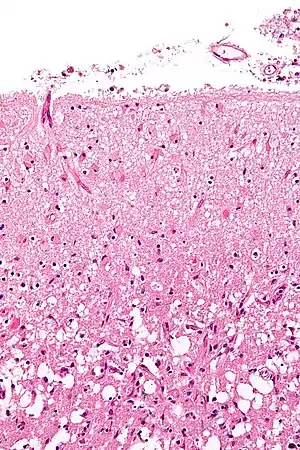

Various microscopic findings are present at times from infarction as follows:[25]

Histopathology at high magnification of a normal neuron, and an ischemic stroke at approximately 24 hours on H&E stain: The neurons become hypereosinophilic and there is an infiltrate of neutrophils. There is slight edema and loss of normal architecture in the surrounding neuropil.

FindingPresence

Eosinophilic (red) neurons 1–35 days

Polymorphonuclear leukocytes 1–37 days

Other acute neuronal injuries 1–60 days

Coagulative necrosis 1 day - 5 years

Spongiosis of surrounding tissue 1 day and older

Astrogliosis (gemistocytes) 2 days and older

Neo-vascularization 3 days and older

Hemosiderin pigment 3 days and older

Mononuclear inflammatory cells 3 days–50 years

Macrophages 3 days–50 years

Cavitation 12 days or older